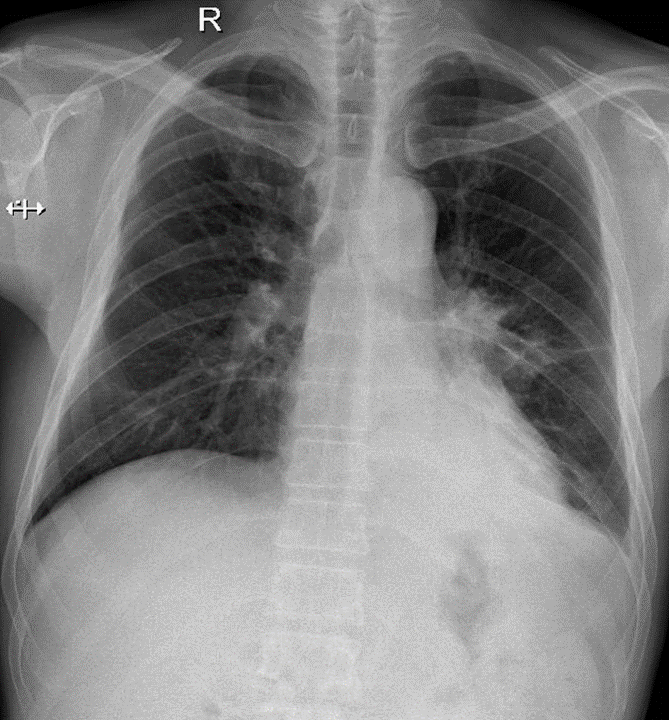

1-Xơ thùy dưới phổi (T) 2- Theo dỏi u rốn phổi (T)